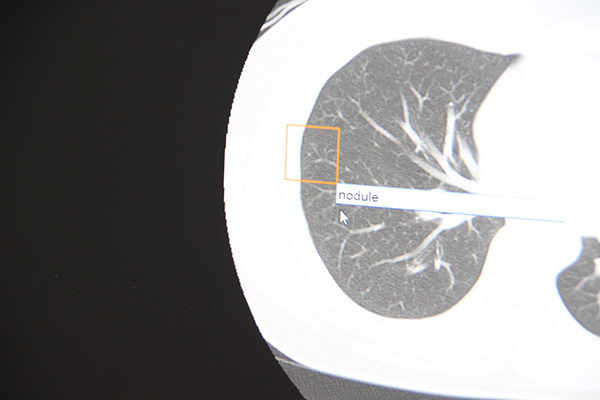

AI-RADのアノテーションツール画面

医師が留意すべき病変部位を記入する。